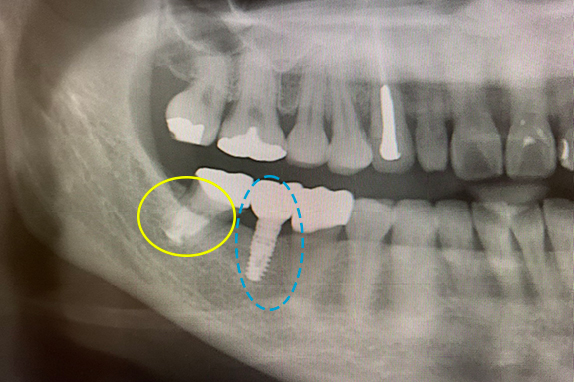

CASE 01 マイクロエンド(精密根管治療)+インプラント治療

-

- 主訴

- 痛くて噛めない(50代女性)

-

- 回数期間

- 6回 約3ヶ月

-

- 治療法

- マイクロエンド(精密根管治療)+インプラント

-

- 治療費用

- 約65万円(税抜)

右の奥歯が痛くて噛めないという主訴で来院。7番をマイクロエンドで完全し6番にインプラントを埋入したケースです。

<リスク・副作用>

術後は顔面の腫脹に加え、青あざができる場合があります。過度な衝撃や咬合を加えると補綴物の破折、脱落の可能性があります。